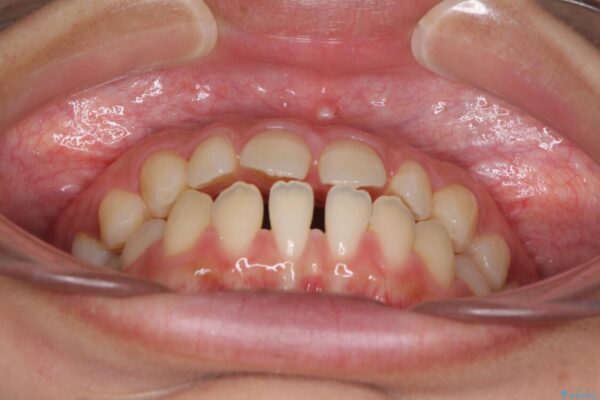

治療前

• 隙間だらけの歯列 インビザラインで改善 治療前画像